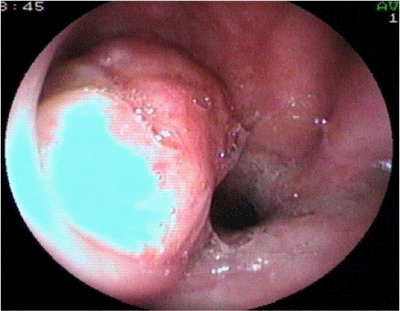

The patient referred right ear fullness and right nasal obstruction. Nasal endoscopy shows a rounded mass in the right wall of the nasopharynx with hyperkeratotic mucosa surrounding the mass. The tumor was affecting the right nasopharyngeal wall, the pharyngeal opening of the Eustachian tube, the posterior floor of the right nasal cavity and the soft palate (Figure 1).

Figure 1 Endoscopic view through the right nasal cavity of a Pleomorphic Adenoma arising in the right lateral wall of the nasopharynx.